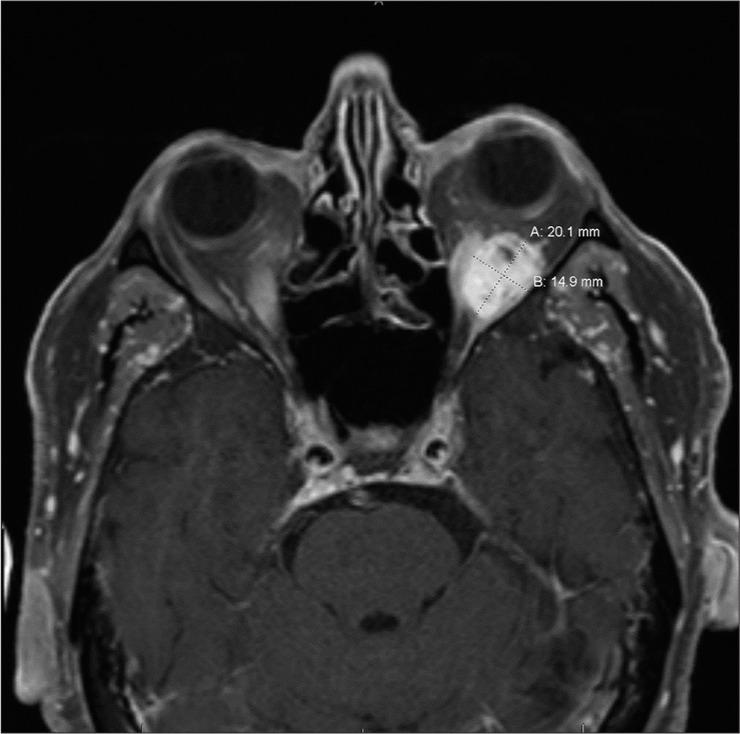

We report a case of a 74-year-old male with progressively painful unilateral proptosis. Imaging revealed the presence of an orbital mass compatible with a thrombosed orbital varix of the inferior ophthalmic vein in the left inferior intraconal space. The patient was medically managed. On a follow-up outpatient clinic visit, he demonstrated remarkable clinical recovery and denied experiencing any symptoms. Follow-up computed tomography scan showed a stable mass with decreased proptosis in the left orbit consistent with the previously diagnosed orbital varix. One-year follow-up orbital magnetic resonance imaging without contrast showed slight increase in the intraconal mass.